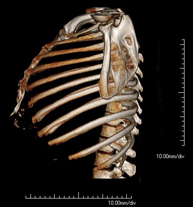

- Ribcage CT

Utilising an X-ray system and detectors that rotate around a patient, this radiological scan generates images that are computer-reconstructed to facilitate a close examination of the ribcage.